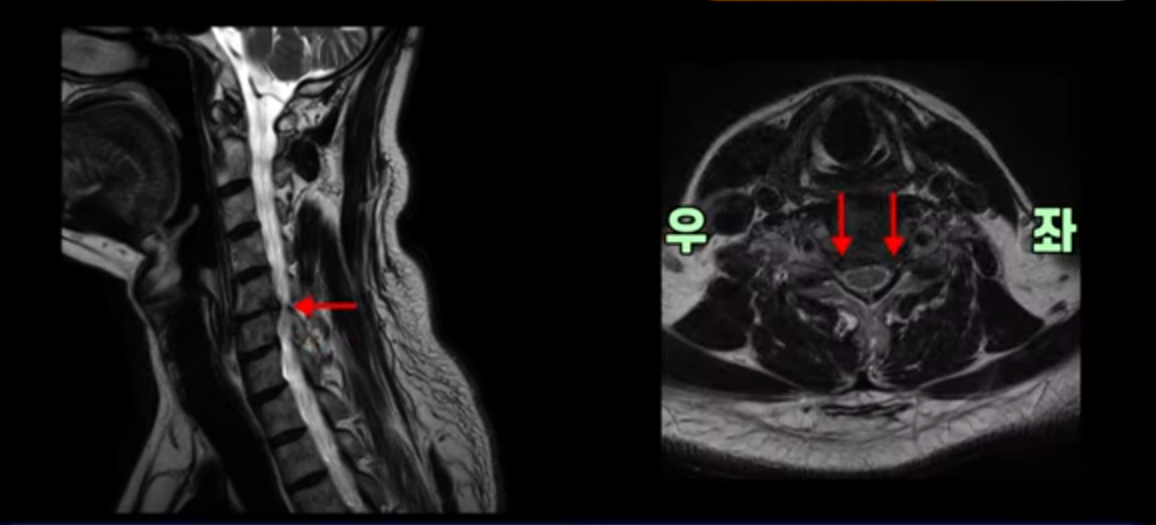

우선 이분 증상은 좌측 어깨와 팔 통증입니다. 이분 MRI를 보면 5번 6번과 6번 7번이 안 좋아 보입니다.

5번 6번에는 오른쪽과 왼쪽 모두 디스크 파열이 있고,

6번 7번에는 왼쪽으로 디스크가 밀려 나와 있습니다.

왼쪽으로 신경이 빠져나가는 추간공을 보면 보시다시피 5번 6번과 6번 7번 신경 구멍이 아래나 위에 비해 막혀있는 게 보입니다.

디스크도 밀려 나와 있고 협착도 있는 겁니다.

이분 왼쪽 어깨와 팔 통증이 갑자기 생긴 이유는 5번 6번 디스크 또는 6번 7번 디스크가 갑자기 밀려 나온 것이 원인일 것으로 보이는데, 그럼 이 디스크들이 밀려 나와서 신경을 자극하거나 누르는데 어떻게 이게 수술 없이도 좋아질 수 있는 걸까요?